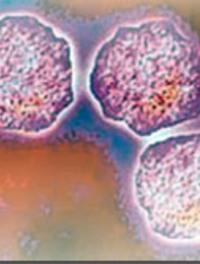

Les dermohypodermites bactériennes nécrosantes-fasciites nécrosantes (DHBN-FN) sont des infections cutanées rapidement progressives rares et graves avec une morbi-mortalité élevée. La principale difficulté réside dans le fait d’établir un diagnostic rapide pour permettre une prise en charge chirurgicale précoce qui conditionne le pronostic fonctionnel et vital du patient. Il faut distinguer, d’une part, les dermohypodermites bactériennes non nécrosantes (DHB) assimilées [...]